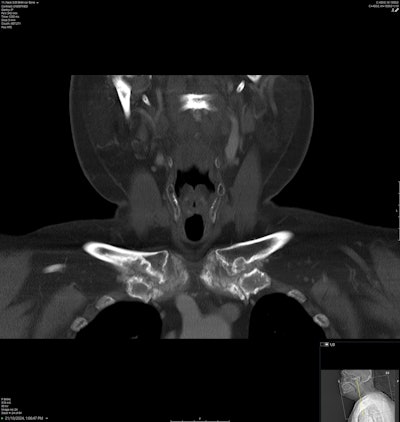

Soft tissue window of a tophus centred in the L2 lamina extending into the neural foramen.

Coronal bone window of the neck demonstrates destructive arthropathy of the bilateral sternoclavicular joints with surrounding partially calcified soft tissue masses in keeping with tophi.